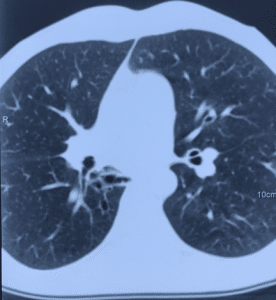

- Мультиспиральная компьютерная томография шеи, органов грудной клетки и/или брюшной полости для обнаружения зоны свища, скоплений жидкости, оценки степени поражения легочной паренхимы, плевральной полости и средостения (рисунок 3).

Рисунок 3. Вторичные бронхоэктазы и пневмофиброз нижней доли правого легкого у пациента с пищеводно-бронхиальным свищом и тотальной ожоговой стриктурой пищевода.